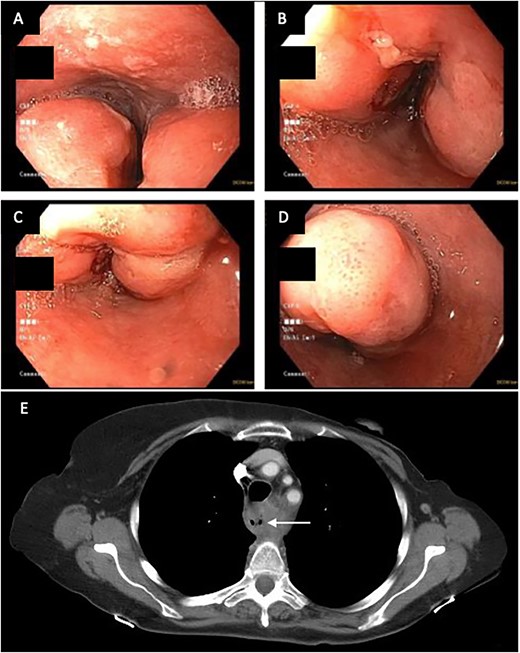

A 71-year-old female presented in May 2020 with a 6-month history of progressive dysphagia and weight loss. Her past medical history was significant for recurrent ductal carcinoma in situ of the left breast. She was a never smoker. Esophagogastroduodenoscopy (EGD) showed a proximal circumferential mass with friable mucosa and ulcerations at 15 cm (Fig. 1A–D). Computed tomography (CT) imaging showed significant soft tissue thickening and luminal narrowing of the esophagus from the sternoclavicular joints to the carina (Fig. 2E). An esophageal stent was placed to support nutrition, which improved the patient’s dysphagia. Biopsy confirmed invasive SCC. Subsequent positron emission tomography imaging revealed 18-fluorodeoxyglucose-avid mediastinal, bilateral supraclavicular, and subdiaphragmatic lymph nodes. Bronchoscopy showed no evidence of tumor invasion into the airway.

(A–D) EDG images showing circumferential esophageal mass with friable mucosa and ulcerations. (E) CT chest showing marked soft tissue thickening with luminal narrowing in the upper esophagus, which extended to a level below the carina.